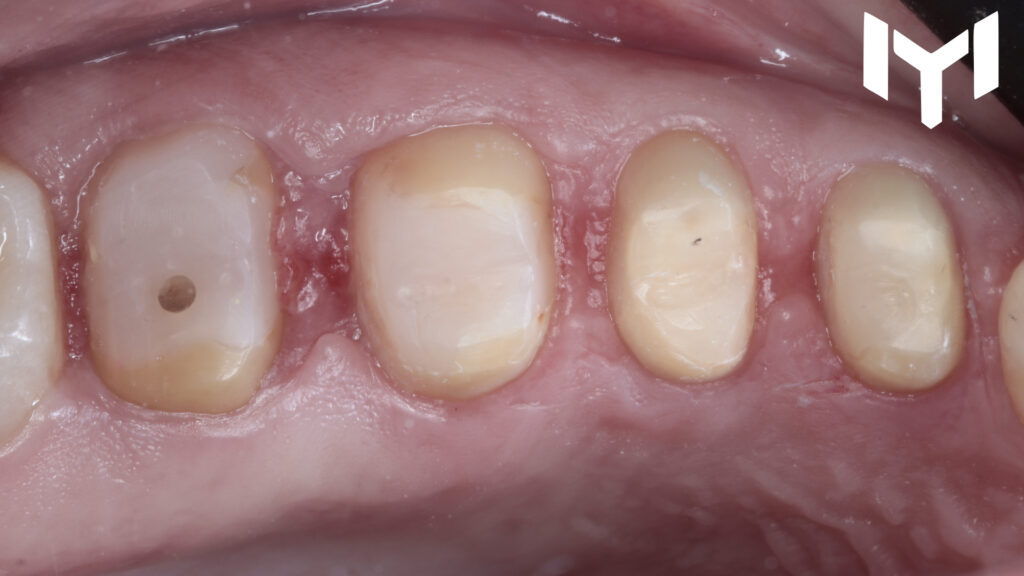

A patient presented with the need for full-coverage restorations on the upper left posterior segment (Teeth 4, 5, 6, and 7). The primary goal was to achieve biological integration and restoring function.

1- vertical preparation for the segment.